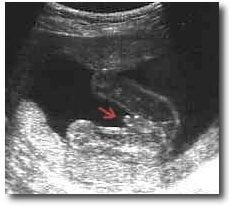

Erkek Bebek